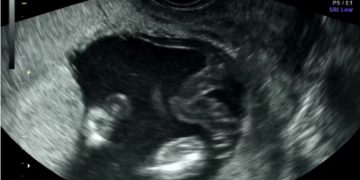

Casi del Mese di Marzo 2023

Cari soci, finalmente online le soluzioni dei casi per il mese di Marzo!!! Grazie a Ilaria Fantasia e Gabriele Saccone!! Caso 1 [pdf-embedder url="https://www.sieog.it/wp-content/uploads/2023/03/caso-clinico-Fantasia-risposta-marzo-2023.pdf" title="caso...